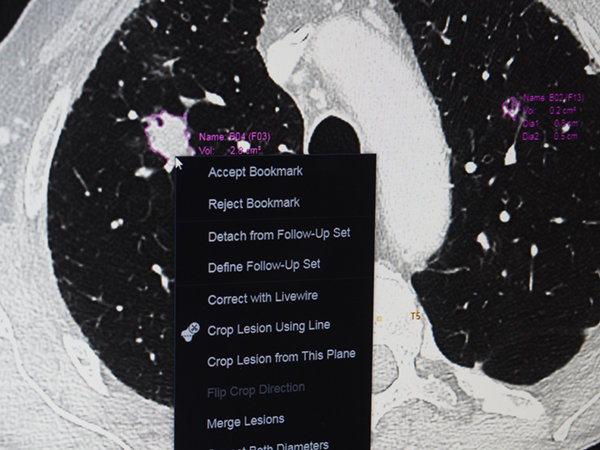

3) CTにおけるLung nodule(肺結節)の自動抽出

胸部CT画像で肺結節を自動で認識し抽出。計測結果はレポートに自動で反映される。従来のビューワでは,結節の選択や計測はセミオートで読影時に選択する必要があったが,AIの自動認識技術で自動化し,計測も自動で行われる。読影医は選択された結節の採否を判断するだけでよく,診断業務をサポートできる。

CTにおける自動でのLung nodule(肺結節)の自動抽出(W.I.P.)